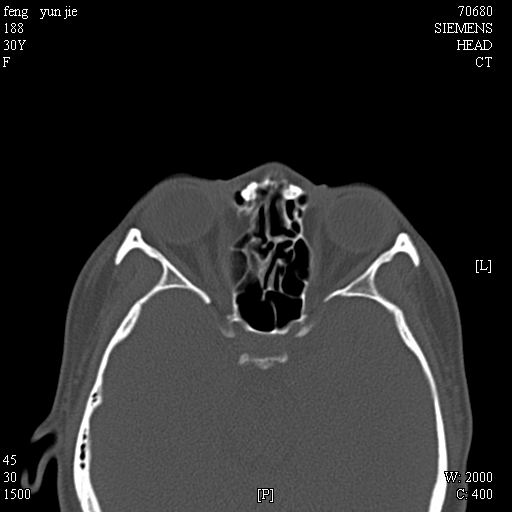

女,37岁,多年前鼻骨骨折过,现在穿刺有炎性分泌物

考虑:1、鼻骨陈旧性骨折;

2、额窦粘液囊肿(右侧水平额窦突入眶内上方)可能性大。

1)左侧鼻骨骨折(陈旧性)。2)双侧额窦及双侧筛窦炎症,伴右侧额筛窦黏液囊肿突入右侧眼眶。